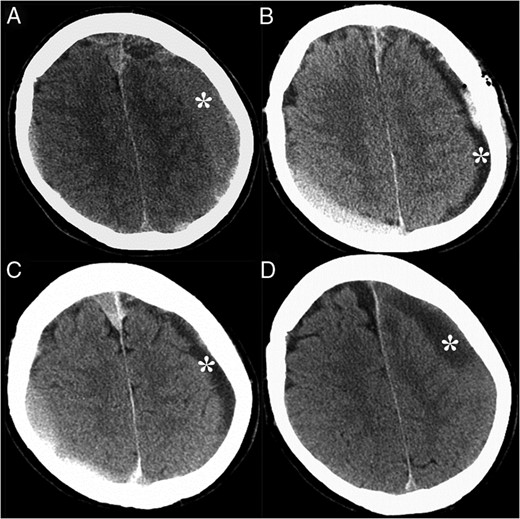

Patient is a 59-year-old male without a significant medical history presenting with a worsening headache and the right lower extremity paresis for the past three weeks. Computed tomography (CT) scans of the brain on admission showed bilateral subdural hematomas (Fig. 1A). A left subdural drain was placed, which led to the marked improvement of symptoms and the CSDH (Fig. 1B). A day later, the drain was removed, and the patient with discharged with the resolution of his symptoms; however, a week following the initial procedure, the patient was re-admitted to the hospital with concerns for increased drowsiness and word finding difficulty. The repeated CT of the head demonstrated what was thought to be a stable left CSDH (Fig. 1C). The patient was discharged home the next day as the work-up at that time was insignificant and symptoms were considered secondary to the opioid use.

CT of the head without contrast demonstrated CSDH, denoted by the asterisks, at the initial presentation (A), after the procedure (B), 7 days later (C) and 4 weeks later, when the CSDH has enlarged (D). Acute subdural hematoma was also noted in the right posterior frontoparietal region.

After 4 weeks of his initial procedure, patient again returned to the hospital with the right-sided hemiparesis and aphasia. Repeated CT of the head was consistent with an enlarged recurrent CSDH (Fig. 1D). Patient underwent a left craniectomy for evacuation of what was thought to be a hematoma. Unexpectedly, after opening of the dura, a large amount of purulent materials was encountered and the diagnosis of subdural empyema was made. Patient was immediately started on broad-spectrum antibiotics for ISDE. He was later switched to intravenous Nafcillin for the duration of 6 weeks, as operative cultures were positive for methicillin-sensitive staph aureus (MSSA). After the 4 months of empyema evacuation, patient underwent a left cranioplasty with an artificial implant to cover the craniectomy defect. Patient was discharged home with an intact neurological exam.